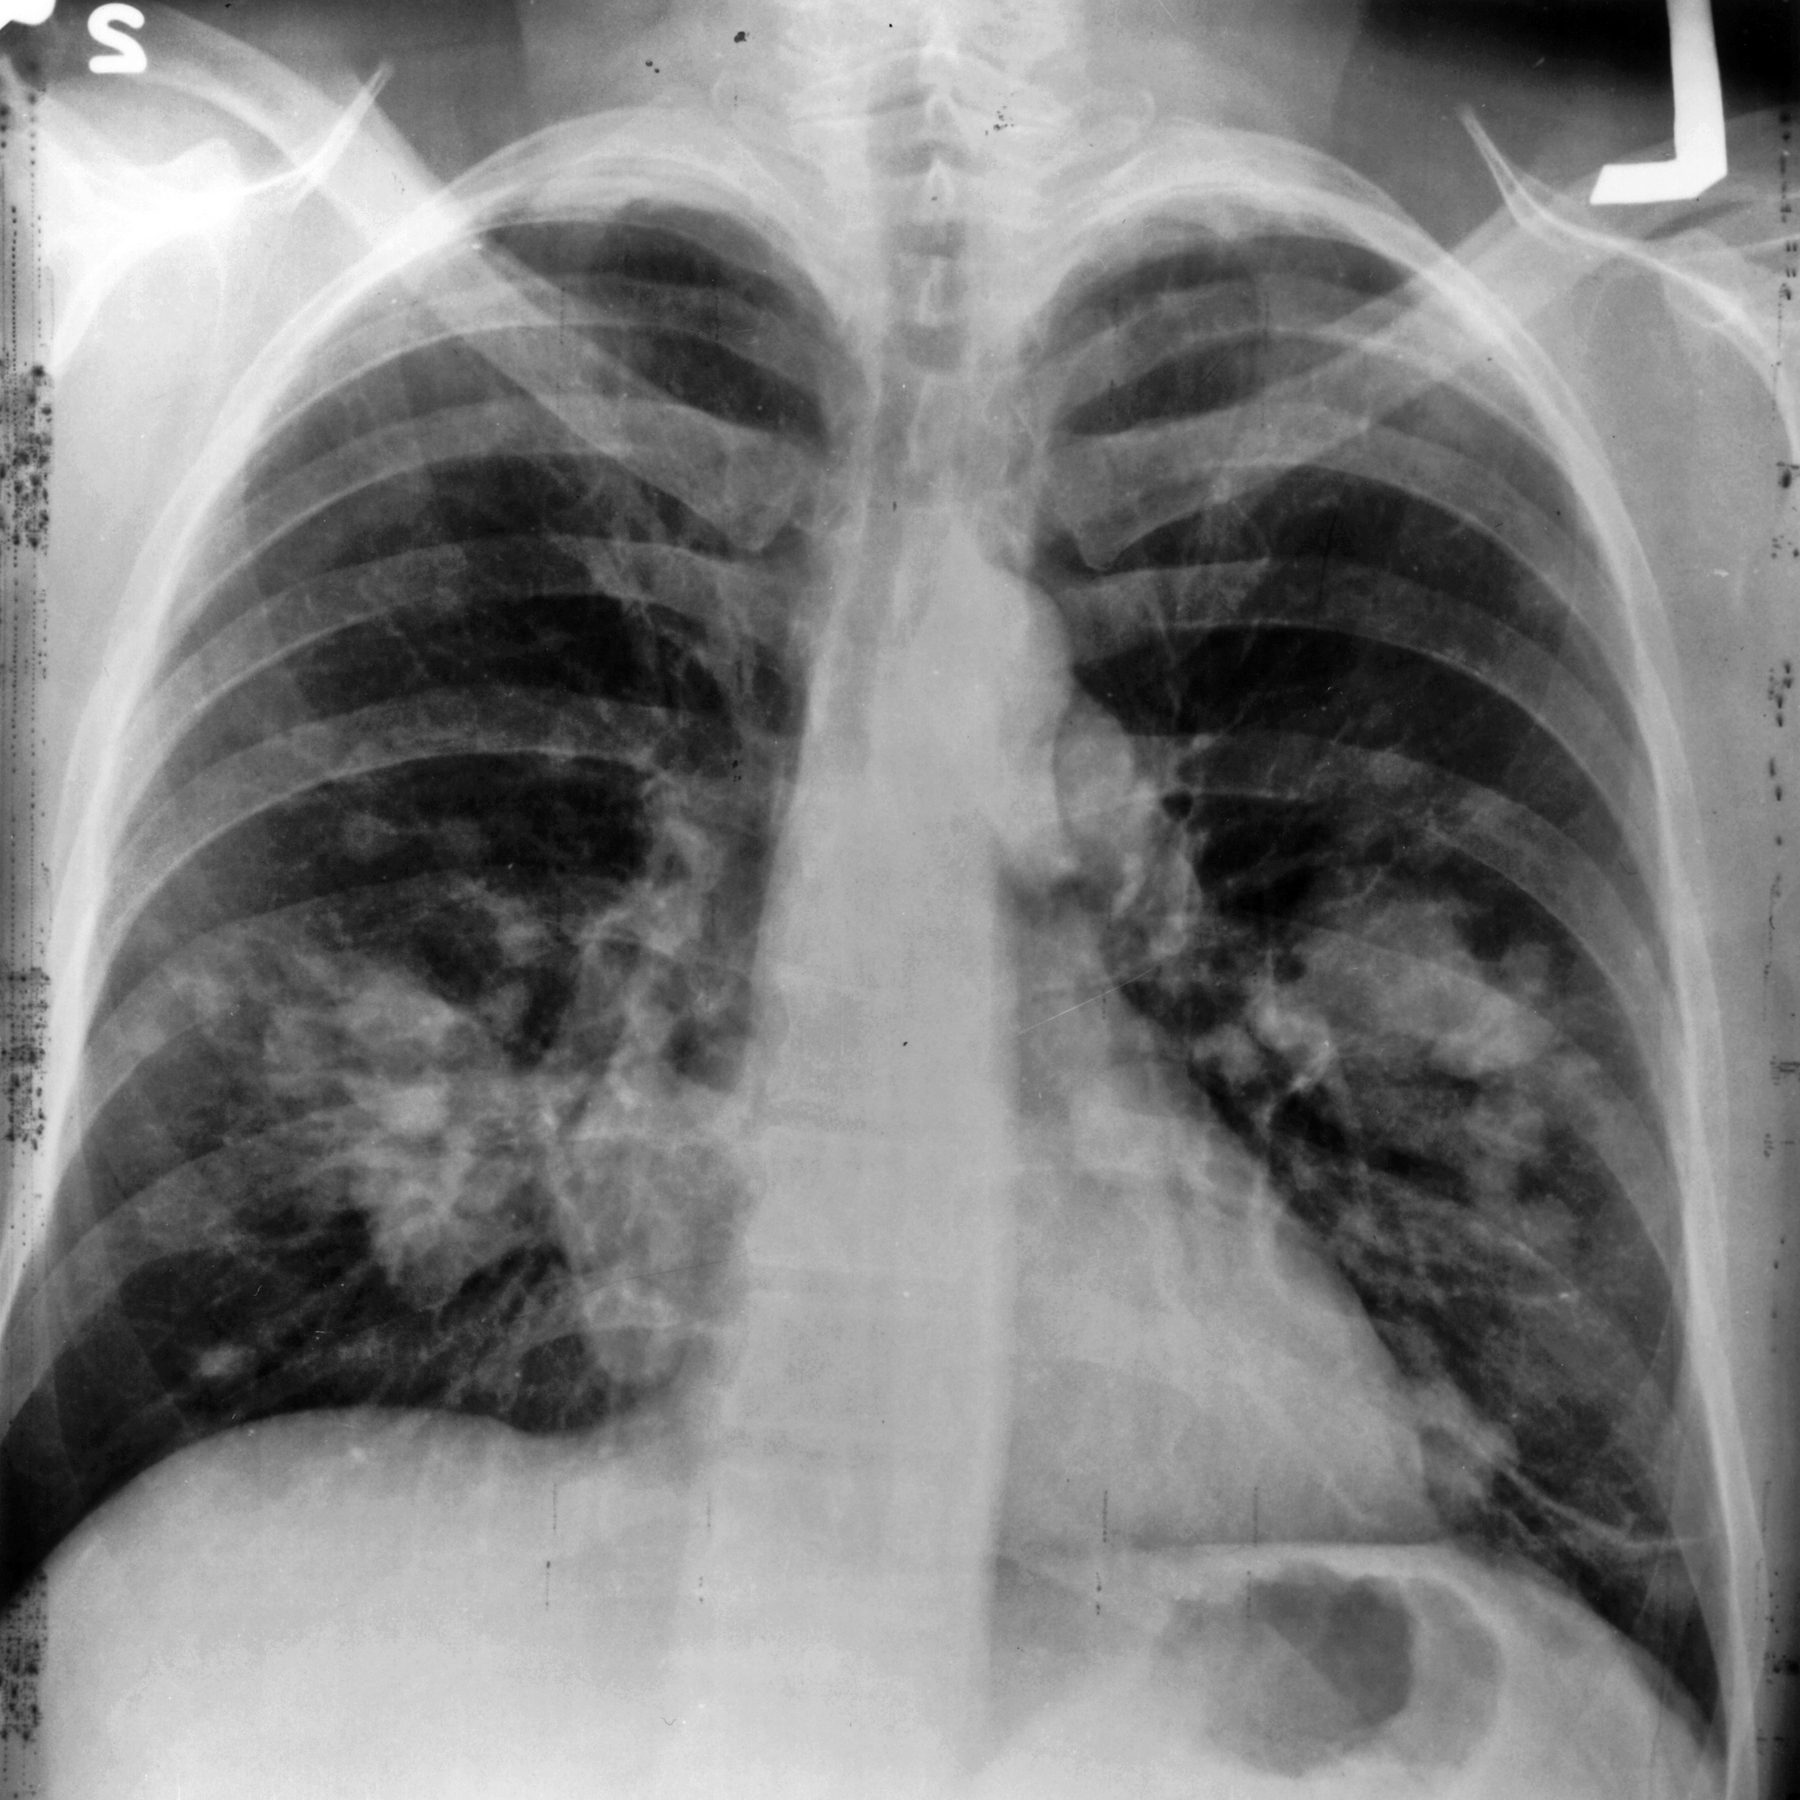

İleri evre akciğer kanserinde "yenilikçi tedavi" dönemi

Akciğer kanserinde bağışıklık sisteminden kaçan tümörlerin tanınmasını ve yok edilmesini sağlayan yeni "immünoterapi" yöntemiyle, özellikle ileri evre küçük hücreli akciğer kanseri hastalarında ortalama yaşam süresinin arttığı belirtildi

İzmir, 2 Kasım 25 (TAK): Bağışıklık sistemini harekete geçirerek tümörün yok edilmesini esas alan immünoterapi yöntemlerinin, özellikle metastaz (yayılma) yapmış ileri evre akciğer kanseri hastalarının ortalama sağ kalım süresini arttırdığı ve yaşam kalitesini yükselttiği belirtildi.